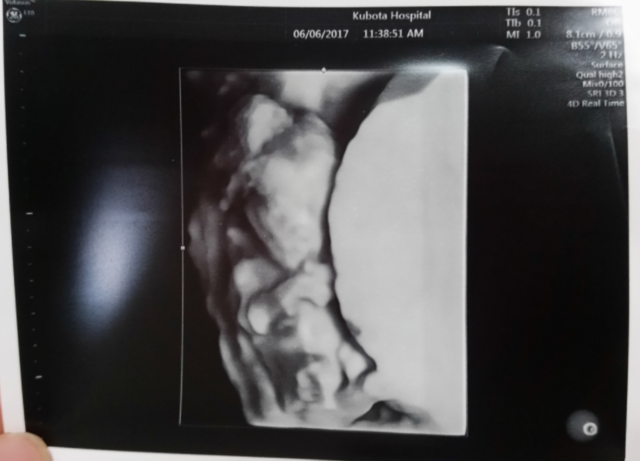

14週0日(14w0d・性別不明)|きなこもっち- さん(32歳)

エコー写真撮影時のエピソード:

病院の都合で、急な転院が決まり転院先で初めてのエコー写真です。新しい病院では、エコーが3Dで見ることができ、立体的な我が子の様子を初めてみて、また動く様子もハッキリと見られてうれしく思ったのを覚えています!

お姉ちゃんになる娘は、まだ分からないようですが、なんとなく感じているのか時々お腹に顔を当てています。まるで、指しゃぶりをしているようなお腹の中の我が子♪早く会いたいです!